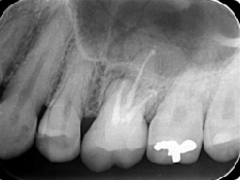

歯周病が進行し、グラグラして物が嚙めず、抜歯してインプラントにしていくことに。

インプラントはストローマンを使用、上部構造はジルコニアセラミックス